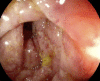

Ischaemic colitis (IC) is the most frequent form of ischaemia of the digestive tract. Due to the worldwide increasing use of medications, there is a growing interest in drug-induced IC. This study reports a rare case of IC directly due to amoxicillin-clavulanate intake. The objective of the study was to describe the evolution of this novel manifestation. An 18-year-old man, non-smoker, with an insignificant medical history, presented with diarrhoea and cramping abdominal pain that started the day following the end of a 10-day amoxicillin-clavulanate course for recent upper respiratory tract infection. Stool cultures including Clostridium difficile toxin testing were negative. Colonoscopy documented an erosive-ulcerative colitis of the sigmoid and the descending colon. Histological examination of the colon biopsies revealed an IC with focal pseudomembranous areas in the descending-sigmoid colon. Thrombophilia screening tests were negative. The patient was discharged from the hospital without symptoms, and another colonoscopy was performed 3 weeks after the previous one, which documented normal endoscopic and histological findings. Amoxicillin-clavulanate IC is a very rare condition and should be suspected once infectious diseases, vascular/haemodynamic causes and a prothrombotic/hypercoagulable state have been excluded. Immediate discontinuation of the antibiotic leads to rapid disease remission.